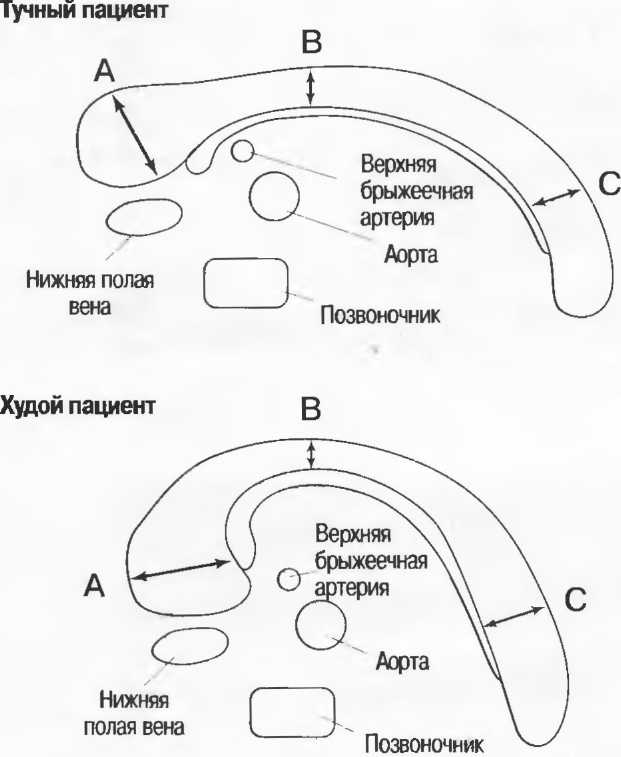

Акустическое усиление и акустическая тень

Чистые жидкости проводят ультразвуковой сигнал без существенного ослабления, поэтому отраженные эхосигналы, идущие от тканей, расположенных за жидкостью, обычно усилены (более яркие). Этот феномен известен как «акустическое усиление» (рис. 10а). Прием достаточного количества жидкости для заполнения желудка дает смещение кишечника, содержащего газ, и тем самым создает акустическое окно. Это особенно полезно для визуализации тела и хвоста поджелудочной железы.